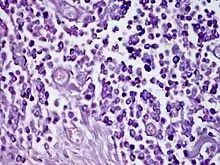

| Solitary mastocytoma. | |